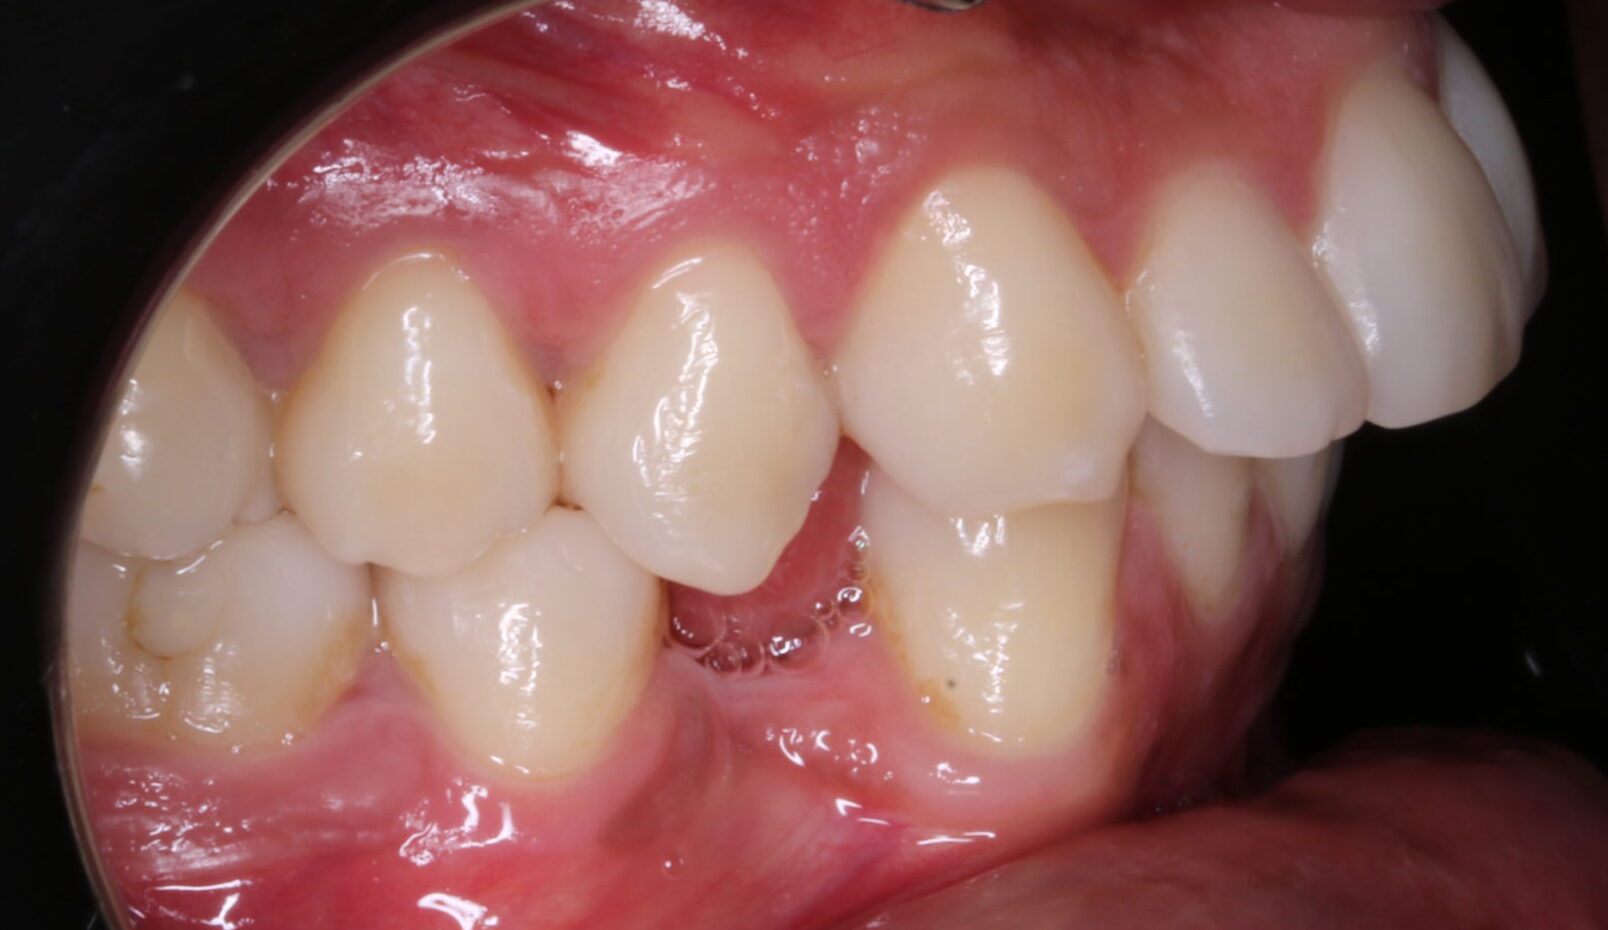

B) En la arcada inferior: la situación es distinta, ya que el paciente, tiene ausencia de 34 y 44. Además  cursa con una desviación de la línea media inferior hacia la izquierda de 3mm. También, en el cuadrante 3, se ha consumido el espacio de dicha pieza ausente, por inclinación corono mesial de 36 y 37 por lo que nos vemos en la necesidad de recuperar ese espacio perdido. Al realizar el estudio, nos damos cuenta que la necesidad retrusión del incisivo inferior es 3,75. ( la norma es 1, y están en 4,7). Además analizamos, la curva de Spee, y para nivelarla necesitamos 0,75 por hemiarcada.

FOTOGRAFÍAS DE INTERÉS